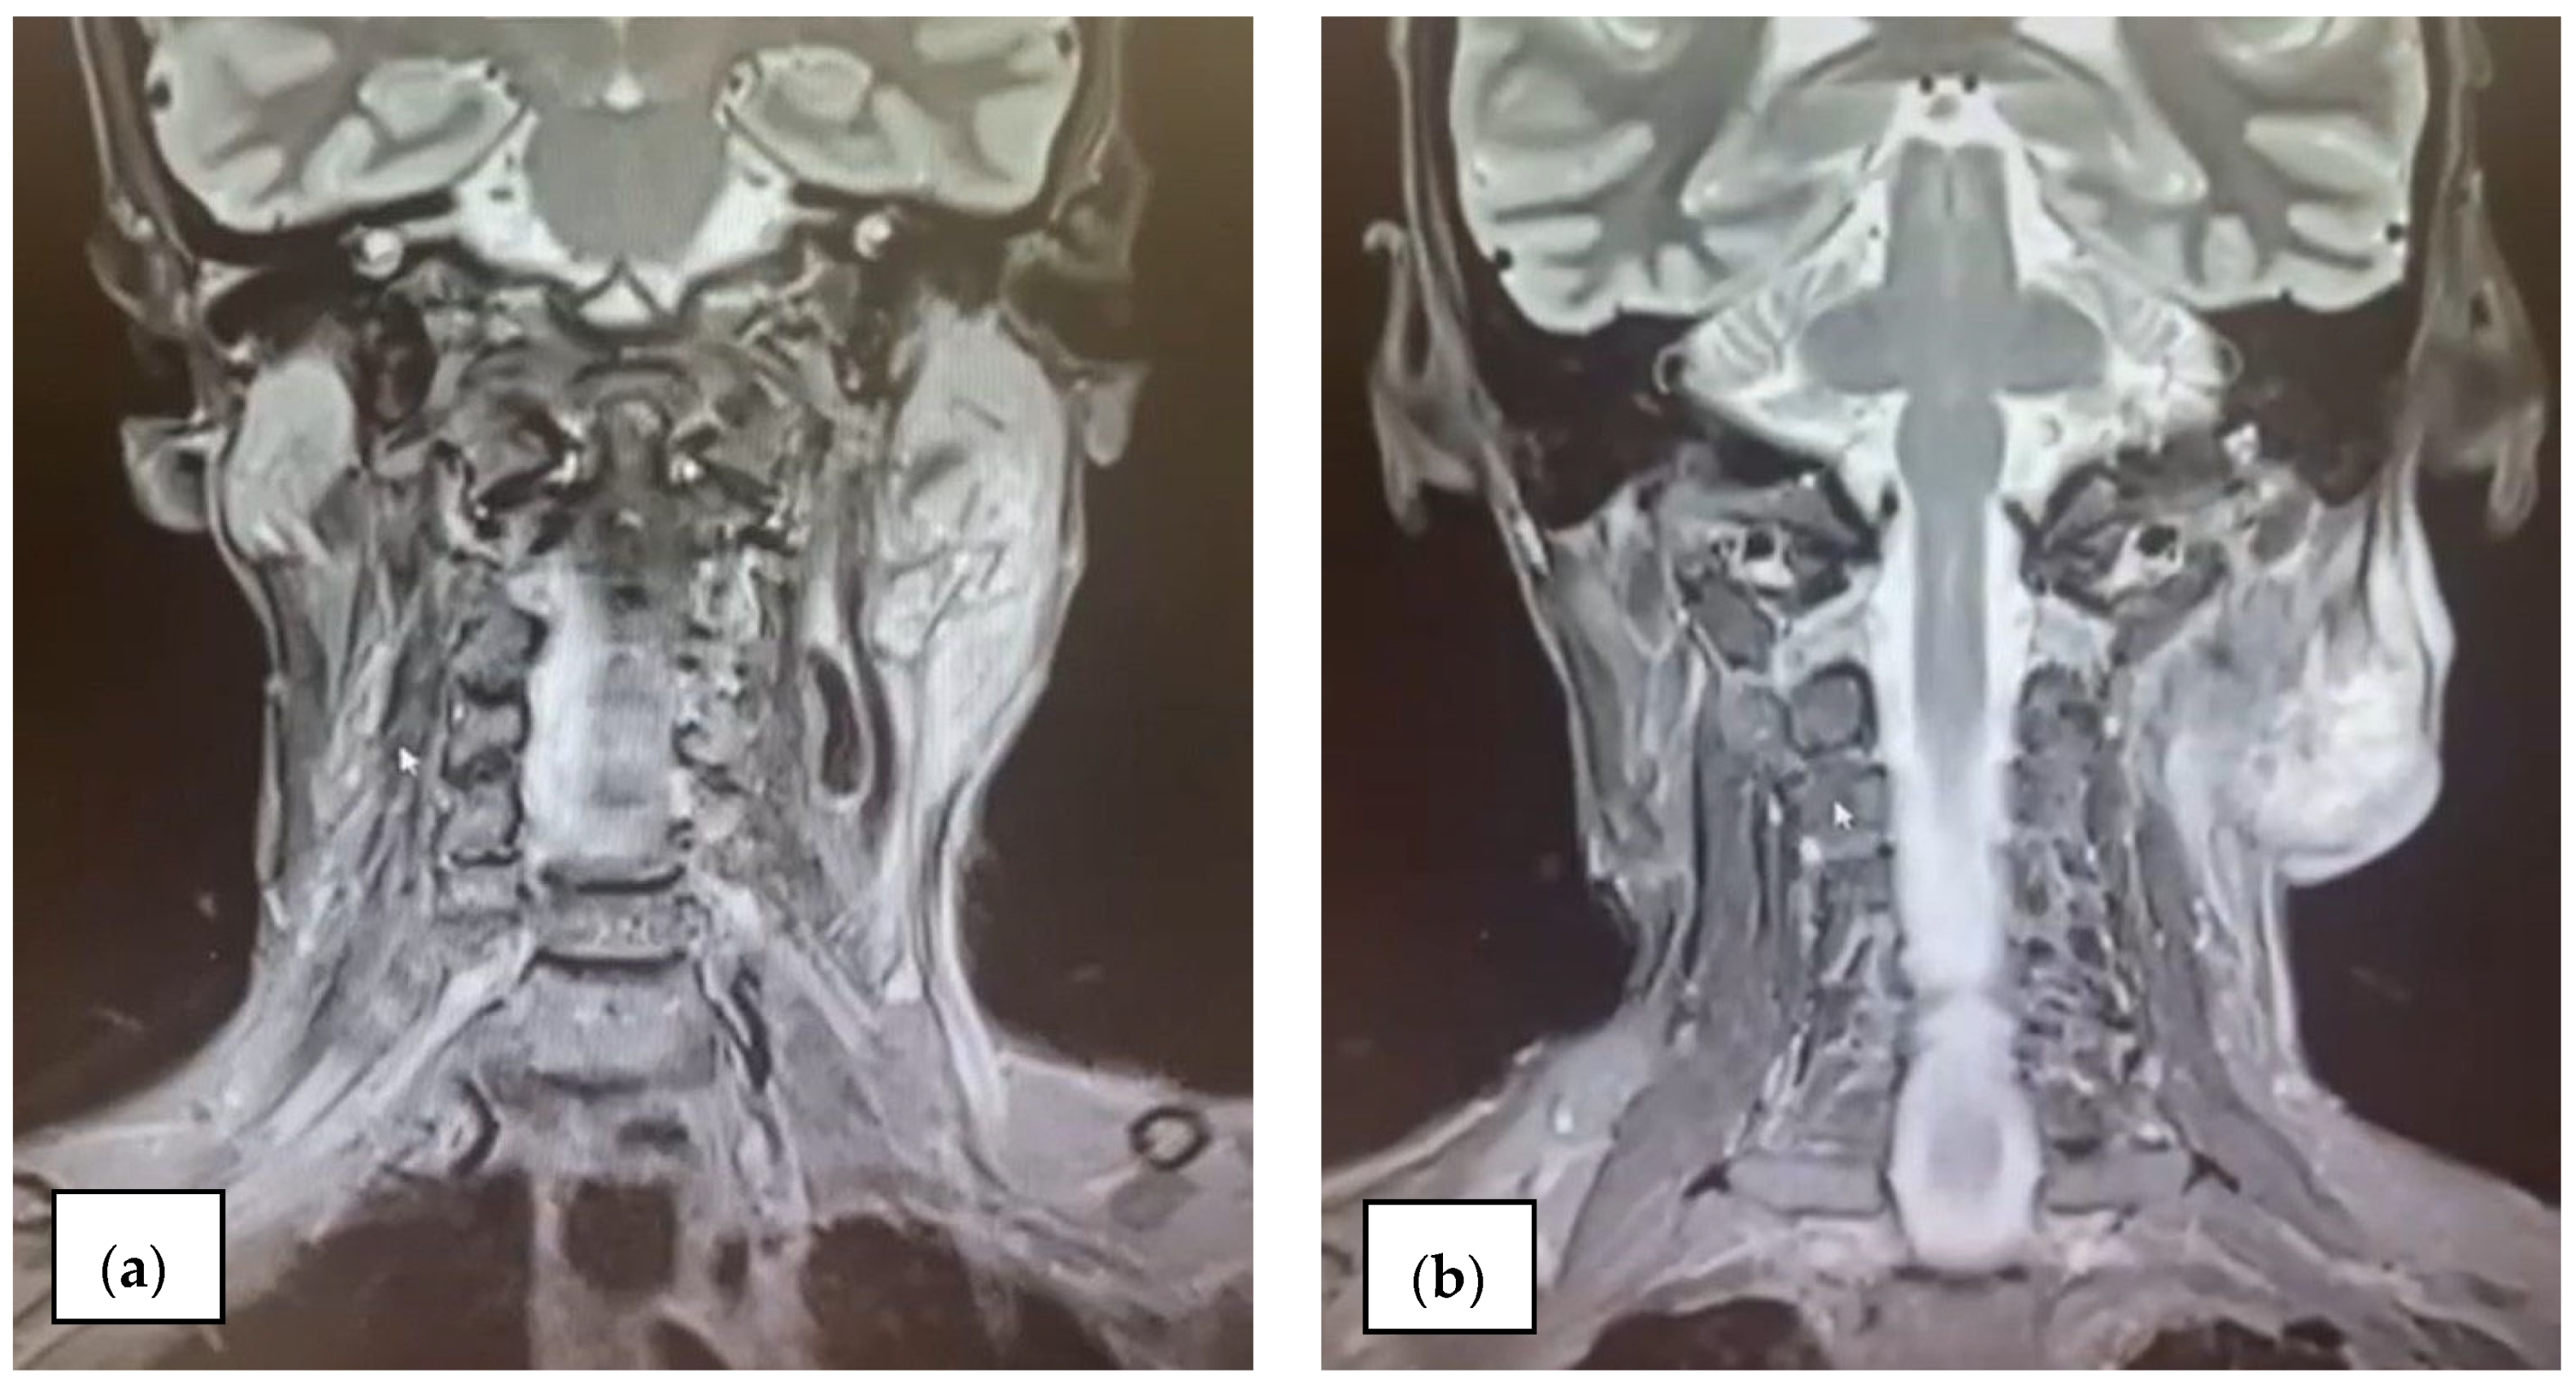

2.3.3. Imaging Findings